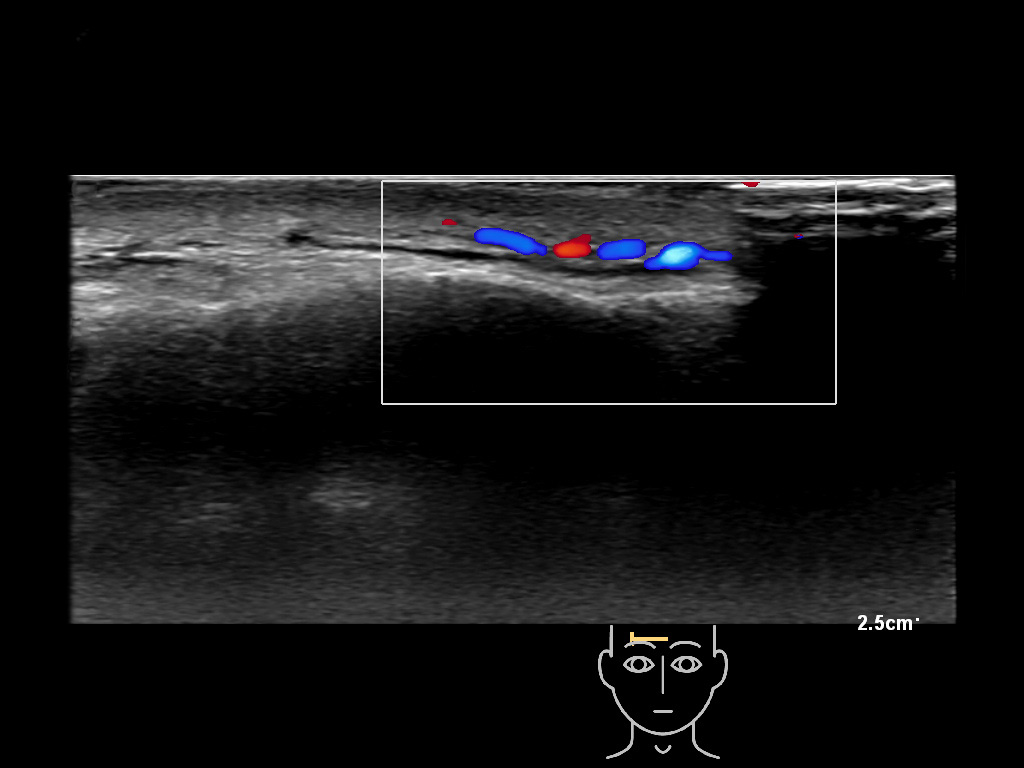

In this section you will learn more about the different layers of the face with the use of ultrasound. When you click on the secondary ultrasound image, you will see the different structures as an overlay. This will help to train yourself to recognize the different layers of the face.

Study the first image to recognize the different layers. If you are sure about the layers, swipe to the second image to view the answer (if applicable).